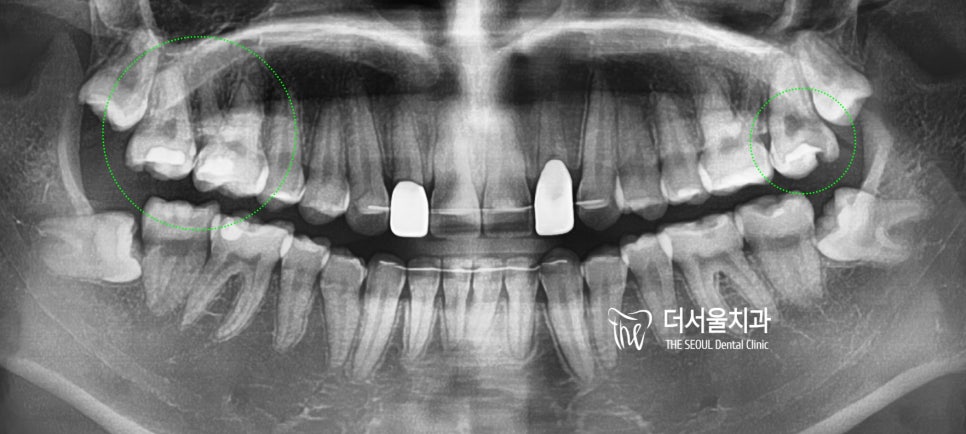

상악 양측으로 구치부(어금니)쪽에서

음식을 먹을 떄 마다 치통이 느껴져서

검진 겸 찾아오신 분입니다.

일단, 치료를 여러 군데 받으신

이력이 관찰이 됩니다.

2. 엑스레이 촬영

일단, 교익 방사선 촬영(Bite wing)을

먼저 실시 했습니다.

그 결과, 육안검진으로는 보기 힘든

인접면 우식증(proximal caires)가

관찰이 됩니다.

더불어서 기존에 수복되어 있던

인레이들의 하방에서도 2차 우식증이

발견이 되는데 이미 그 크기가 커져서

2개의 어금니는 신경치료까지

진행을 해야 되는 상황이였습니다.